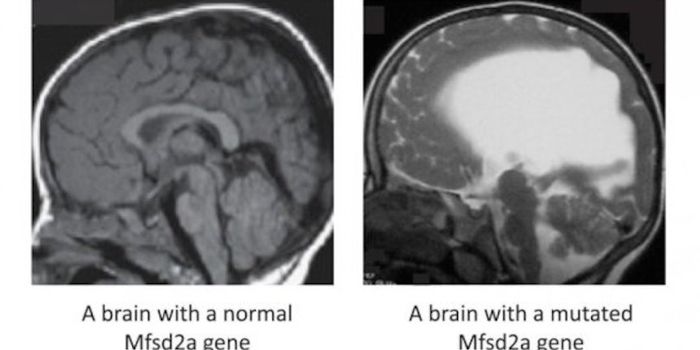

JUL 17, 2015NeuroscienceWhat causes autism? Is there something physical that accounts for behavioral differences?

Researchers have gr ... -